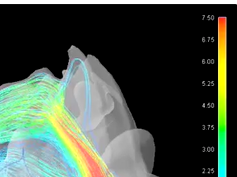

Laryngeal Electromyography-Guided Hyaluronic Acid Vocal Fold Injection Procedure

- Date : 01/01/2020

- 0

0